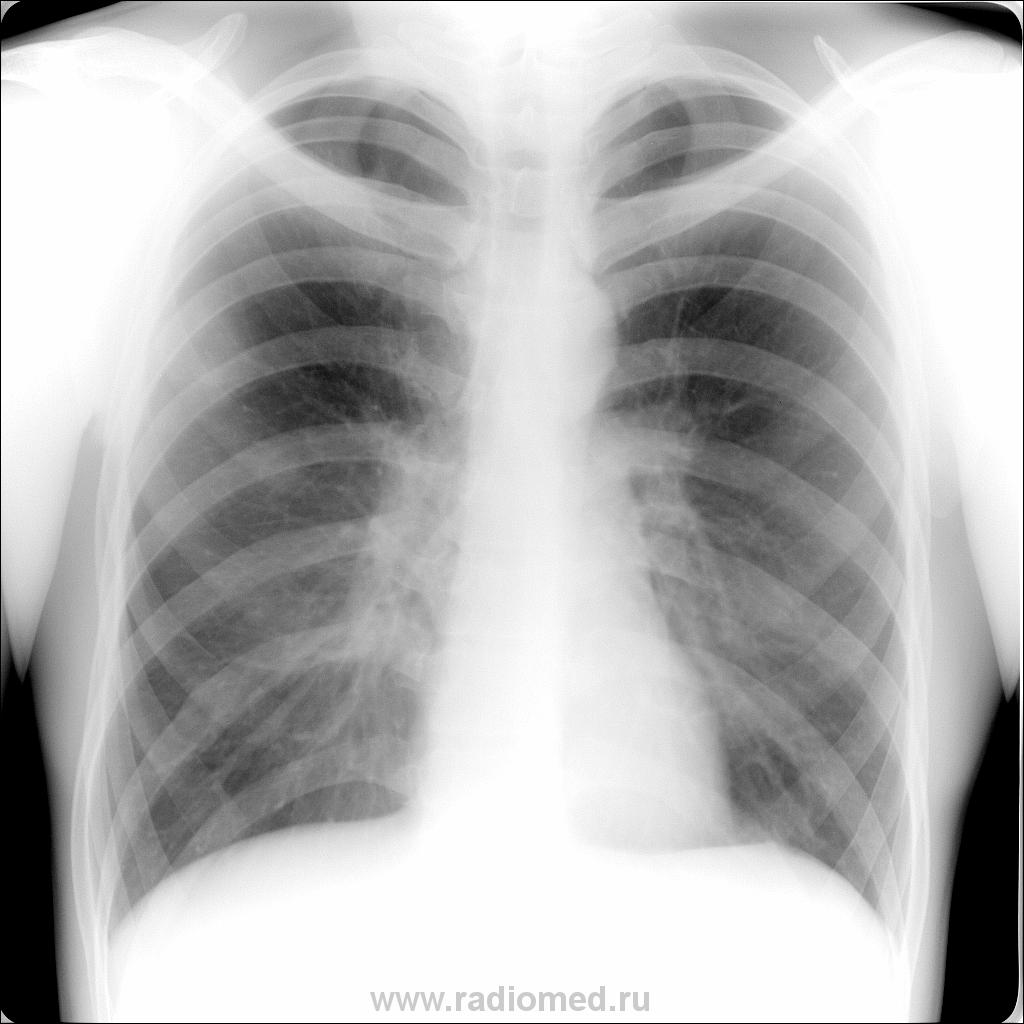

Здравствуйте, коллеги. Молодой человек 1989 г.р. приболел в декабре 2010г. 20.12.10г. сделан снимок. Болен около двух недель: потливость, недомогание, покашливание, периодический под"ем температуры до субфебрильных цифр, особенно по вечерам. СОЭ 15 мм/ч, L 9,5. Какие будут мнения?

Инфильтративный туберкулез ах.субсегмента справа? Схема стандартная - противовоспалительное неспецифическое лечение и контроль через 2 недели, если нет хорошей динамики - к фтизиатрам.

По боковому непонятно, в каком сегменте инфильтрат.DS-?

Инфильтрация малоинтенсивная, поэтому на боковой не видно. Но сублевральное расположение на прямом снимке практически не оставляет сомнения в Sax.

В оконцовке, терапевт не стал связываться с туберкулезом (изоляция и все такое) и отправил в туб. отделение. На дорожку сыпанул ему горсть антибиотиков. Больной возвратился через две недели с "теплым приветом" от фтизиатров. Что же, стандарт есть стандарт.

Пока пневмония-потом видно будет.